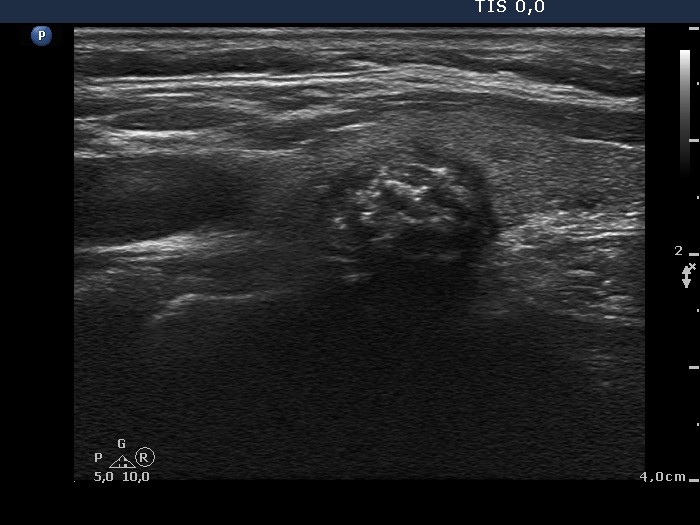

Benign colloid goiter (cytological diagnosis)

This nodule presents different types of hyperechogenic granules, the ventral figures are either comet-tail artifacts or punctate echogenic foci, while although the primary focus cannot be seen, the acoustic shadows prove that there are coarse calcifications, as well.